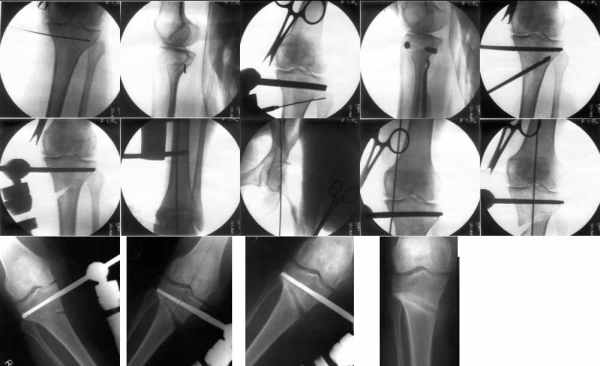

I do upper tibial osteotomies with either an ilizarov fixator and acute correction of the deformity or with an orthofix with gradual correction.

Sending you pics of the steps of the osteotomy and the frame.

You can do the osteotomy in a "focal dome" or in a transverse fashion. The dome has the advantage of having a good contact, allowing weight bearing as tolerated early on.

The level is below the tibial tuberosity.

The frame I use is pretty simple, with one wire each in the proximal and distal ring, two schanz pins in the proximal ring, and one each in the middle and distal ring.

I preconstruct a frame with the proximal ring in varus by the use of coupled washers in the threaded rods in the front and back. These are used as hinges, and after the correction, a medial and lateral threaded rod is also added.

Since the center of rotation of these deformities is usually near the knee joint line, lateral translation of the distal fragment is necessary to normalise all the axes.

You can also do the osteotomy in a transverse fashion.

When I use an orthofix fixator, the osteotomy is oblique, starting below the tuberosity and ending 1 cm away from the lateral cortex at the level of the head of the fibula. No fibular osteotomy is needed there. The deformity is gradually corrected over 2 or three weeks.

You could also do the same with an ilizarov fixator

Посмотрел я картинки:(

Это не эстетика.

Это рубка леса и лучевая болезнь.